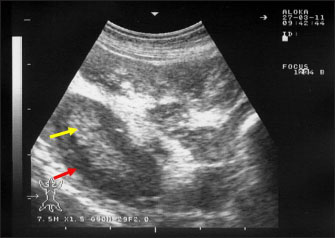

Ultrasonography has been proven effective for the early detection of several abdominal and thoracic disorders in small ruminants (Tharwat et al., 2012b; Tharwat and Al-Sobayil, 2017; Tharwat, 2021; Sadan et al., 2023; Tharwat and Al-Hawas, 2024a,b; Tharwat et al., 2024; Tharwat et al., 2025b). Recently, the technique has been found valuable for the diagnosis of various bacterial and parasitic infections in ruminants (Tharwat and Tsuka, 2024). An overall increase in intestinal mucosa thickness was detected in goats with PTB. It was classified as either mild, moderate, or severe (Fig. 2). Corrugation and folding of the intestinal mucosa may be also imaged in goats with PTB (Fig. 3). However, remarkable enlargement of the mesenteric lymph nodes are the most important findings in goats with PTB (Fig. 4). Other sonographic changes included increased hepatic brightness, intestinal edema consolidated lungs, and pleural, peritoneal, and pericardial effusions (Tharwat et al., 2012b).

Fig. 2. Ultrasonography of the thickened intestinal walls in a goat with paratuberculosis. Thickening of the intestinal mucosa is apparent cross sectionally (red arrows).

Fig. 3. Ultrasonography of the corrugated intestinal mucosa in a goat with paratuberculosis. The lesion (red arrows) was best imaged longitudinally

Fig. 4. Ultrasonography of the enlarged mesenteric lymph nodes in a goat with paratuberculosis. The enlarged lymph node showed a hypoechoic cortex (red arrow) and a hyperechoic medulla (yellow arrow).